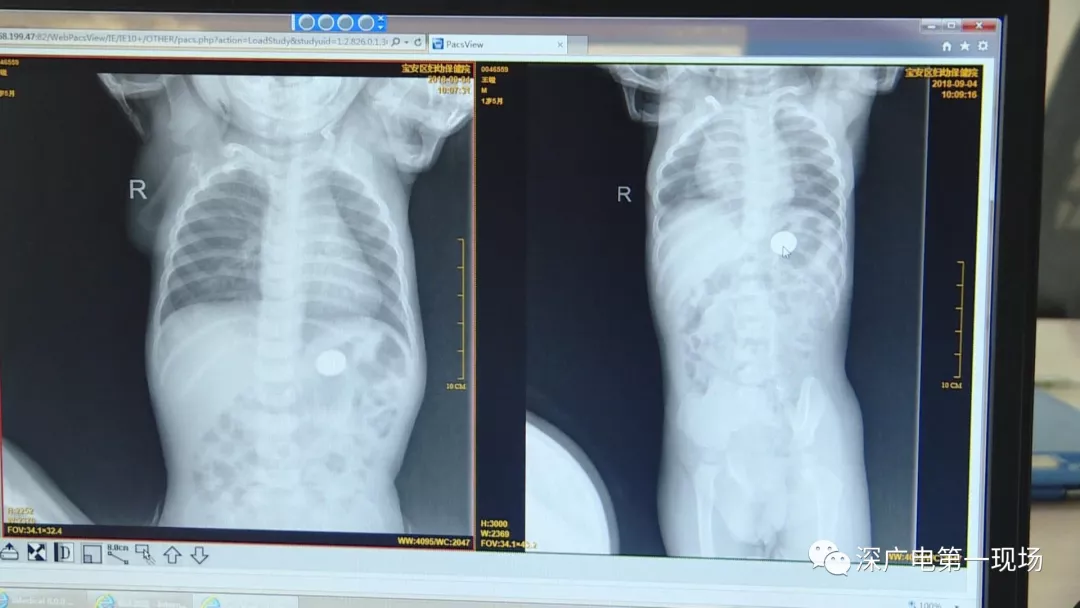

9月4號(hào),一名1歲零5個(gè)月的男嬰因在家中摔傷,被父母送到了寶安區(qū)婦幼保健院,醫(yī)生診斷為左側(cè)尺橈骨骨折。在進(jìn)行全麻手術(shù)之前,院方例行對(duì)嬰兒進(jìn)行了周身檢查。手術(shù)前,兒外科醫(yī)生趙冠聰在查看患者的胸片時(shí),發(fā)現(xiàn)這名嬰兒的胃部有一枚硬幣大小的暗影。

經(jīng)過(guò)兩個(gè)小時(shí)的時(shí)間,兒科醫(yī)生郭景濤為患兒取出了藏在胃底的一角錢(qián)硬幣。目前,患兒已經(jīng)痊愈出院。